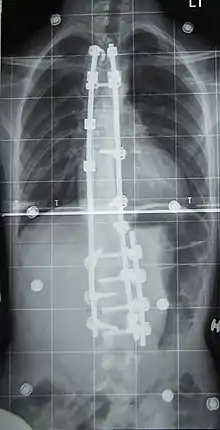

Chirurgie

L'indication concerne environ 10 % des scolioses idiopathiques du sujet jeune[2] et concerne les scolioses importantes, avec un angle de Cobb dépassant les 50°. La technique consiste en la mise en place de deux longues tiges métalliques vissées dans les vertèbres, permettant le redressement de la colonne vertébrale, notamment avec la technique et le matériel de 3e génération proposés par Cotrel et Dubousset[45]. Les complications sont essentiellement locales mais il peut exister des étirements ou compressions de racines nerveuses dans moins d'un pour cent des interventions[46].

À l'issue de l'intervention (qui peut dans certains cas corriger totalement la scoliose), le rachis est bloqué de manière définitive. Les vertèbres libres de greffe devant travailler davantage pour « compenser » l'immobilisation du reste de la colonne, des douleurs dans le dos peuvent apparaître de façon imprévisible et à tout âge. Le rachis étant un flexible conçu pour bouger - et non être bloqué, on considère que l'opération ne règle pas entièrement le problème : on supprime un défaut (la courbure) pour en créer un nouveau : la rigidité du dos liée à l'opération.